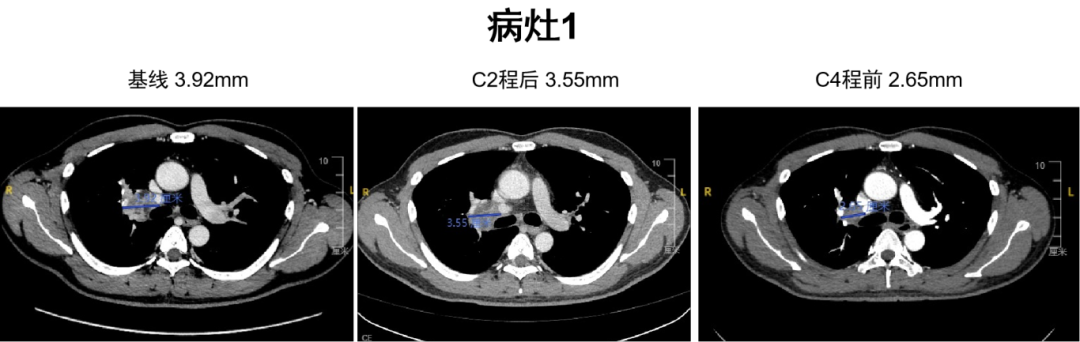

C2程后影像学评估为SD,C4程前为PR。

图片6.png

图3 病灶1影像学评估